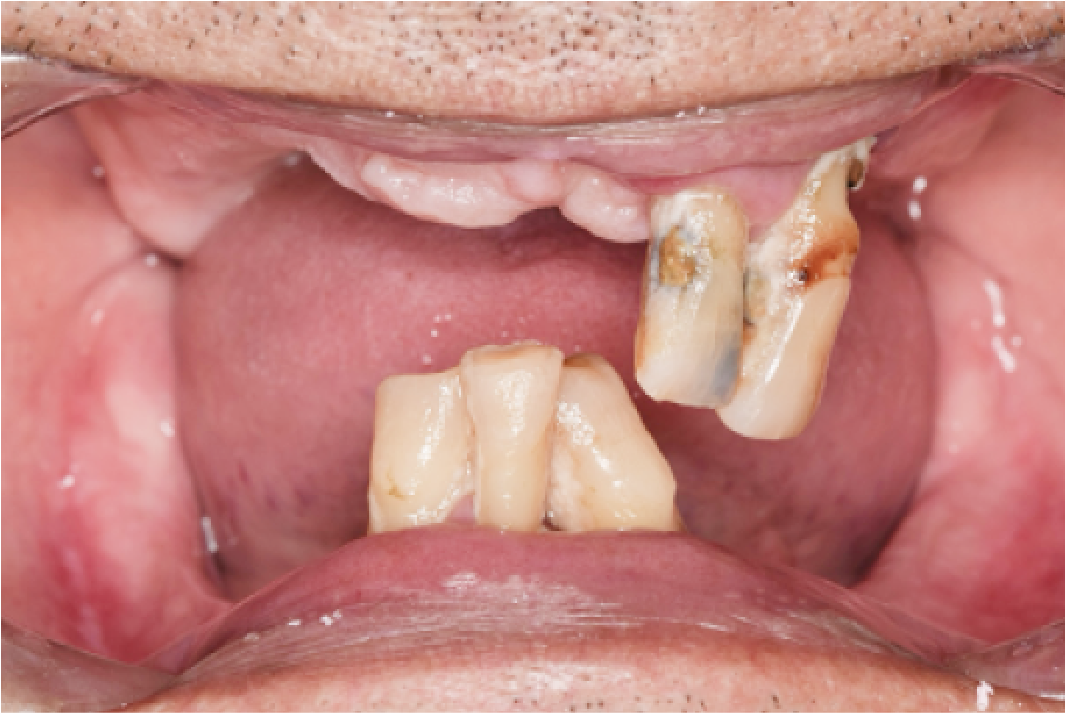

CASE04

■ 治療内容

上下顎All-on-4インプラント治療

■ 治療費用

6,627,000円(税込)

■ 治療期間

約9ヶ月

■ リスク

治療後の腫れや出血、またメンテナンスを怠ることで周囲炎のリスクあります。